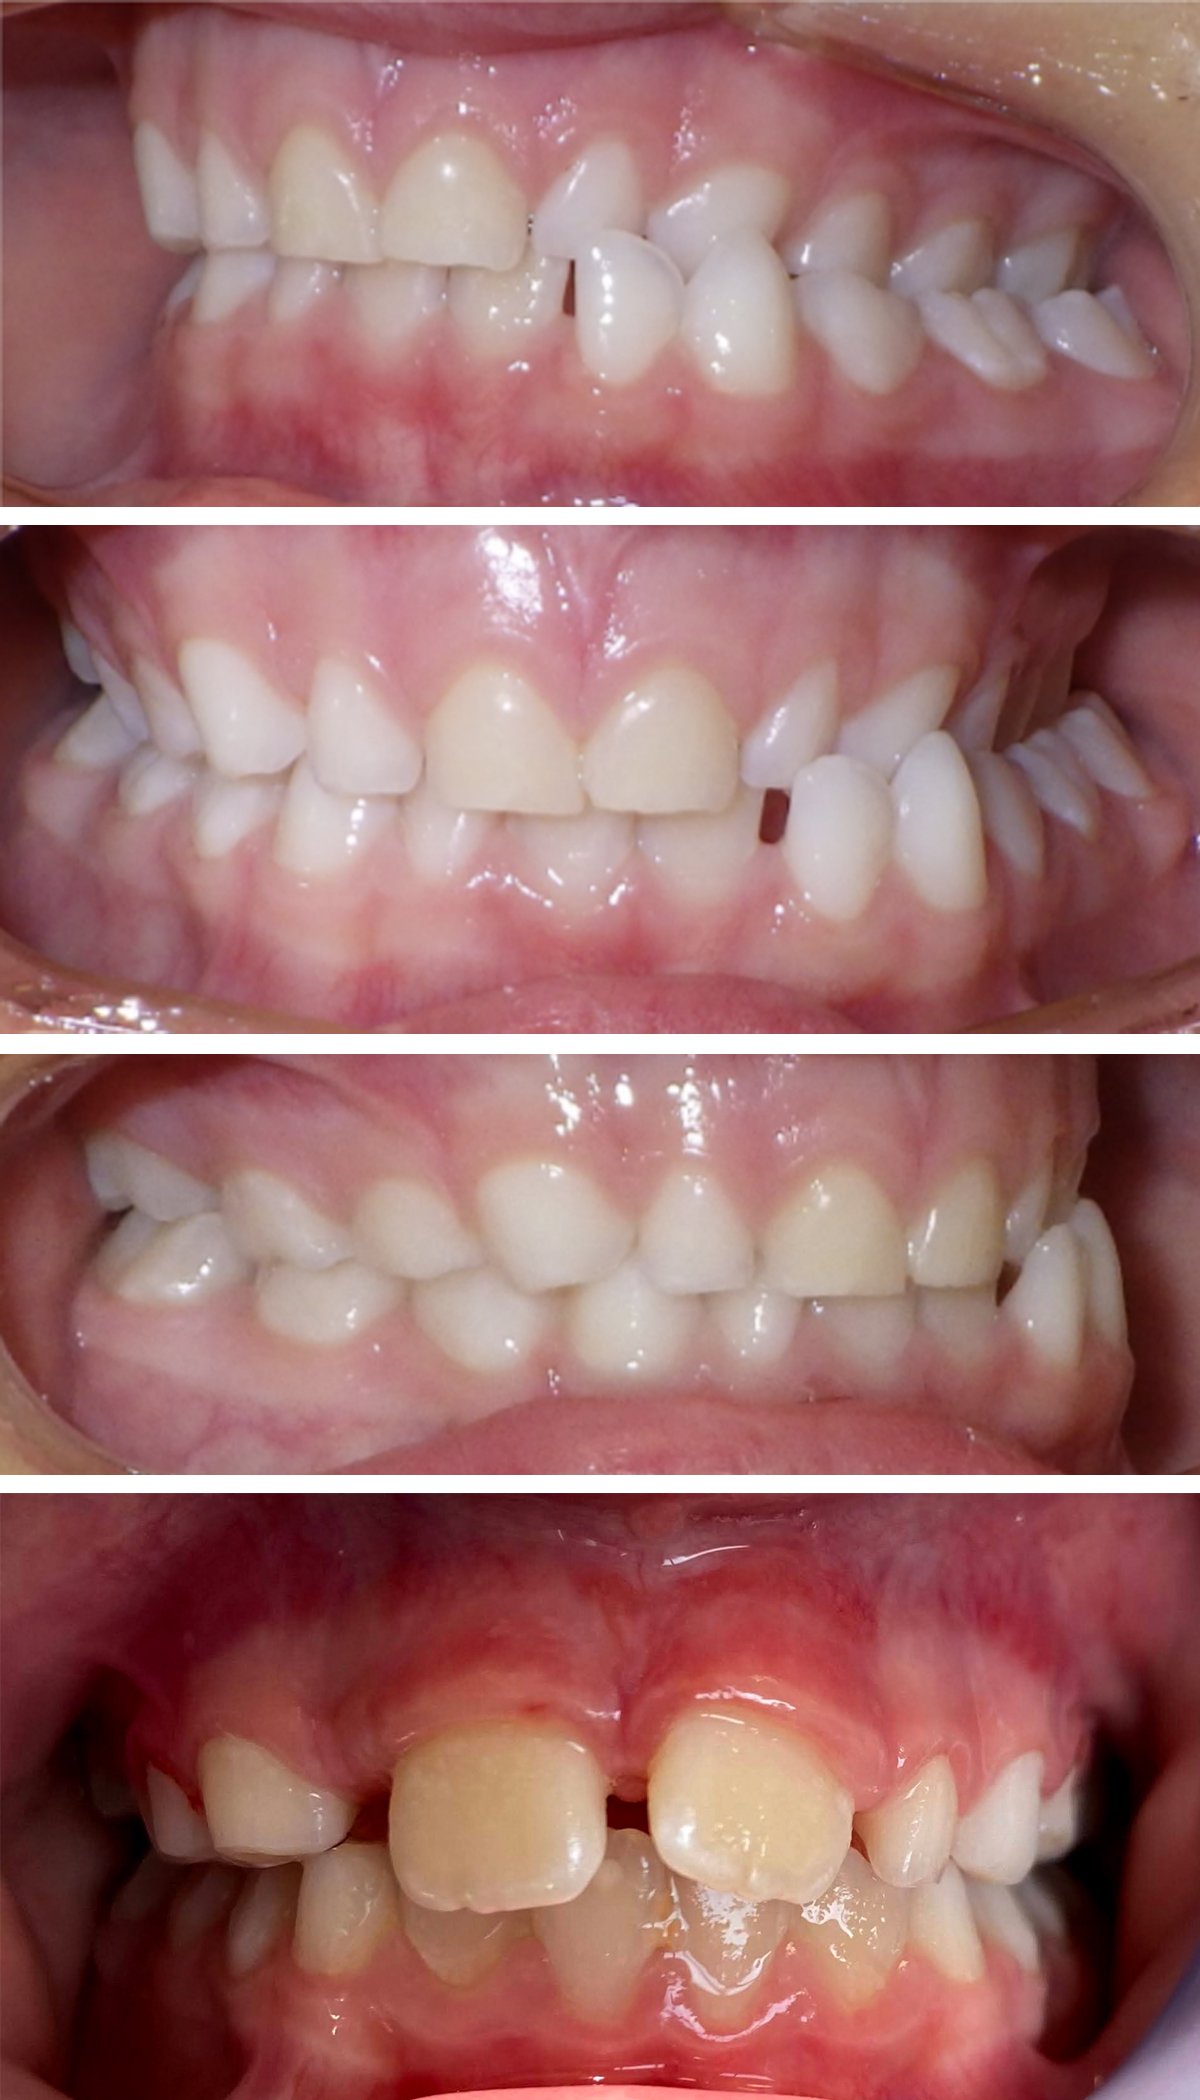

Orthodontics

Movement of teeth to improve function and appearance with Invisalign

Invisalign

Before and after appliance

Orthodontic Appliance